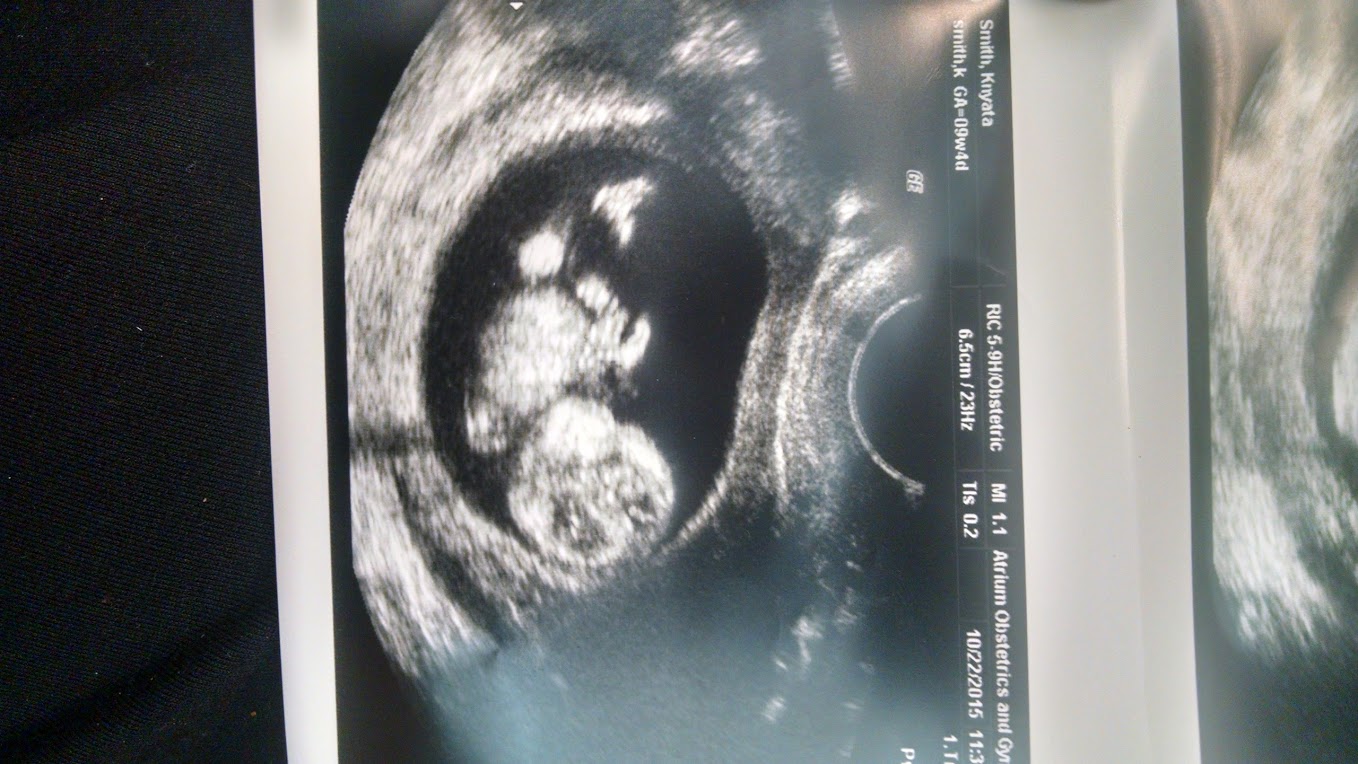

We had our first ultrasound yesterday, baby is measuring right on track for a due date of 5/18. I'm 10 weeks today. Strong heart beat too! Loved seeing our sweet, little one for the first time!

Finally had our ultrasound yesterday. 9 weeks exactly! HB is 163 BPM. I was so nervous walking into that room that something may have been wrong. I am so thankful and feel so blessed that our baby is healthy! :x :x

9 weeks 5 days. Got to see bean's heartbeat and a little movement!!! Idk what was sweeter, seeing the movement or the look on my husband's face when it happened! I'm on cloud 9 today!